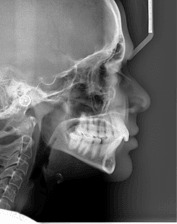

Телерентгенография (CEPH)

Телерентгенографията (CEPH) е профилна снимка на черепа. Обикновено се прави на деца за нуждите на ортодонтията. По нея лекарите измерват и анализират захапката, планират необходимите корекции и проследяват развитието на челюстите и зъбите.